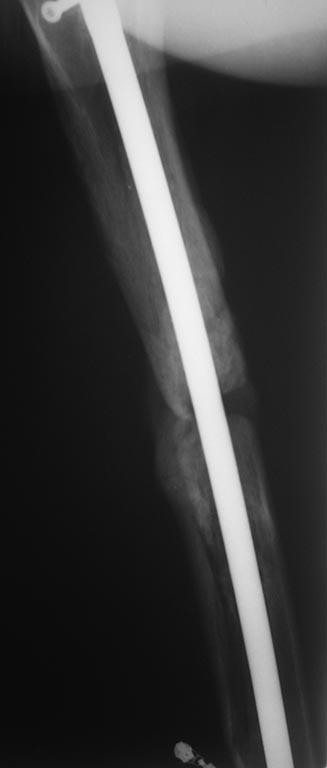

С возросшей регулярностью на форуме обсуждаются «беспричинные» случаи несращения переломов после интерлокинга. В постах больше внимания уделяется обсуждению тактике дальнейшего лечения. Причём в подобных случаях предлагаемые варианты не отличаются многообразием и ограничиваются либо таким же остеосинтезом только стержнем большего диаметра, либо пластинкой с костной пластикой либо внеочаговой фиксацией. К сожалению, почти всегда остаются без анализа возможные причины, приведшие к несращению. А жаль. Ведь вероятность сращения после интерлокинга приближается к ста процентам, и точно установленная причина, почему это не произошло в положенные сроки, может подсказать тактику дальнейшего лечения. С моей точки зрения, безусловной причиной несращения перелома бедренной кости в обсуждаемой случае является оставшаяся подвижность между проксимальным и дистальными фрагментами после остеосинтеза. На это указывает и сам больной. Причём очаг нестабильности расположен в проксимальном костном фрагменте между ним и проксимальным концом стержня. Хотя на первый взгляд кажется, что вся проблема в дистальном костном отломке, точнее в отсутствии стабильности между ним и дистальным концом стержня из-за значительной разницы в диаметрах стержня и костномозгового канала. На последних рентгенограммах чётко видна костная мозоль между латеральным кортикальным слоем и стержнем на входе в костномозговой канал дистального отломка. Она говорит об эффективности дистального блокирования тремя блокирующими винтами в полифокальных плоскостях. И на сегодня биомеханическая система дистальный отломок – стержень работает как единое целое. Формируется новый костномозговой канал в дистальном отломке по ходу дистального конца стержня за счёт образования костной мозоли между латеральным кортикальным слоем и стержнем. И этот формирующийся костномозговой канал точно соответствует диаметру стержня, что является дополнительным фактором, стабилизирующим дистальный конец стержня. Поэтому, с моей точки зрения, не имеют смысла предложения, направленные на введение каких-либо металлоконструкций, уменьшающих размер костномозгового канала дистального отломка. Да и сделать это технически при такой рентгенологической картине крайне сложно, если вообще возможно. Что касается проксимального блокирования. Крайне неудачно проведен самый проксимальный блокирующий винт. Если авторы рассчитывали на последующую динамизацию (что, при таком переломе крайне неразумно), то его надо было проводить по верхнему краю овального отверстия. Если предполагалось статическая фиксация на протяжении всего периода сращения, то было бы разумнее его провести по нижнему краю овального отверстия. Тогда нагрузка при передвижении больного распределялась бы на оба проксимальных блокирующих винта, что снизило бы вероятность их перелома. Я уже писал в предыдущих постах с похожими случаями. Два блокирующих винта во фронтальной плоскости, один из которых проведен через овальное отверстие, не могут обеспечить стабильность во фронтальной плоскости, если костномозговой канал на выходе из проксимального отломка не соответствует диаметру стержня. И это, с моей точки зрения, служит наиболее частой причиной несращения. И это же служило причиной частых несращений при фиксации тонкими стержнями без рассверливания костномозгового канала. В данном случае мы бы рассверлили канал до диаметра канала на выходе из проксимального отломка (13-14 мм) и имплантировали бы стержень такого же диаметра как последнее сверло. Отдаю предпочтение протезированию всей длины бедренной кости с дистальным блокирование в мыщелках. Лучший вариант, с моей точки зрения, – реконструктивный стержень с проксимальным блокированием в шейке бедра двумя винтами. Хотя допустим и обычный стержень с расположением винта в овальном отверстии по его нижнему краю. Режим фиксации, безусловно, статический.

Непохоже. Вверху он нормально держался, и внизу центрального отломка канал неширокий. Подвижность явно была, но скорее всего, больше за счет расколотого и длинного периферического отломка, винты-то далеко, а рычаг длинный. В сочетании с неустранненным смещением по ширине, отсутствием кортикальной аппозиции по латеральной стенке даже достаточно активного костеобразования здесь не хватило, чтобы стабилизировать отломки.